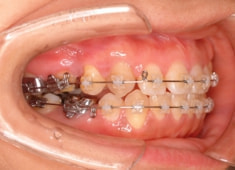

治療開始時